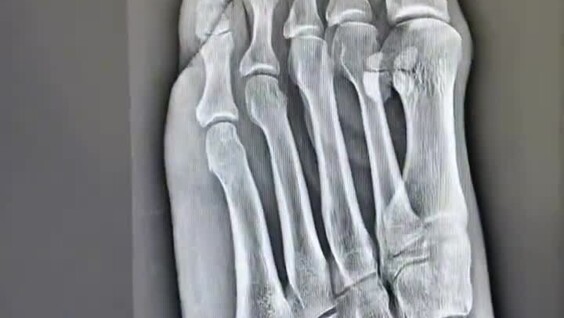

Он пришёл без записи, с распухшим пальцем и искренним удивлением. Через двадцать минут его уже принял травматолог, сделали рентген прямо в здании, наложили фиксатор и выдали обезболивающее и всё бесплатно. Общее время от входа до выхода составило менее часа. Видео, где он с восторгом показывает чистый кабинет, отсутствие очередей и ноль рублей на кассе, набрало за неделю несколько миллионов просмотров.